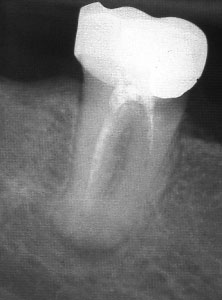

При добре проведено ендодонтско лечение кореновият канал е запълнен точно до стеснението, разположено на 1 - 1.5 мм. от края на канала - т.нар. физиологично стеснение. Не бива да остава незапълнена част от канала. Много често се получава припресване на канлопълнежното средство извън канал на зъба, в тъканите около корена.

Рентгенографии на добре пролекувани зъби

Винаги е необходимо лекуващият да се стреми към този резултат: